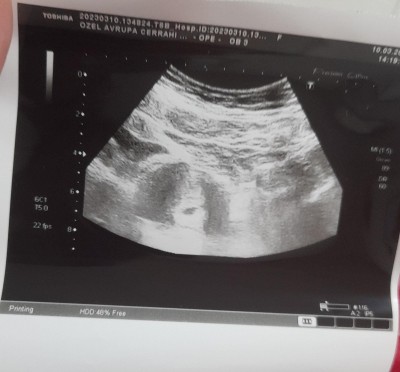

2 Martta devlet hastanesinde yatış verildi kese görünmüyor yavaş yükseliyo 7 haftalığa göre, dış gebelik olabilir dediler. Kabul etmedim yatışı. Özele gittim 1398 çıktı daha 5 haftalık normal dedi ve keseyi gördü. 24 Mart ta kalp atışlarını duyarız dedi. Özele gitmeye devam edicem ama sizce nasıl yükselme?

Gebelik haftası 6